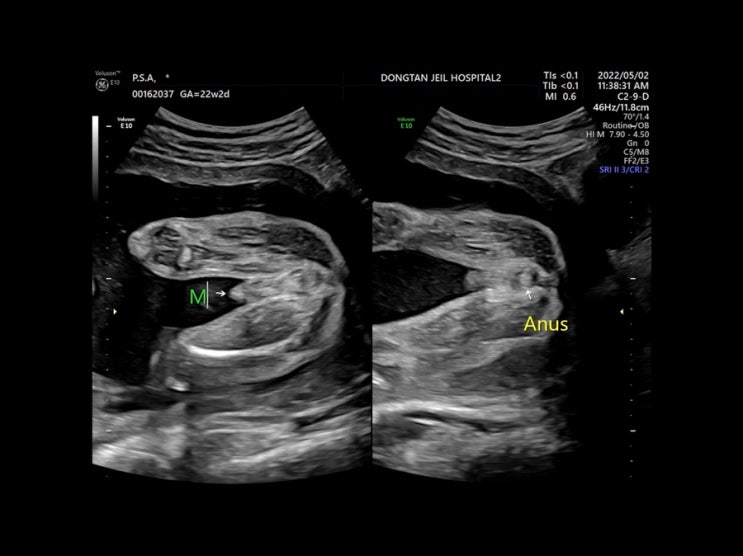

[임신일기] 임신 중기 정밀초음파

임신 중 21주에서 24주 사이가 되면 임신 초기 기형아검사만큼 중요한 임신 중기 정밀초음파가 진행된다. ...